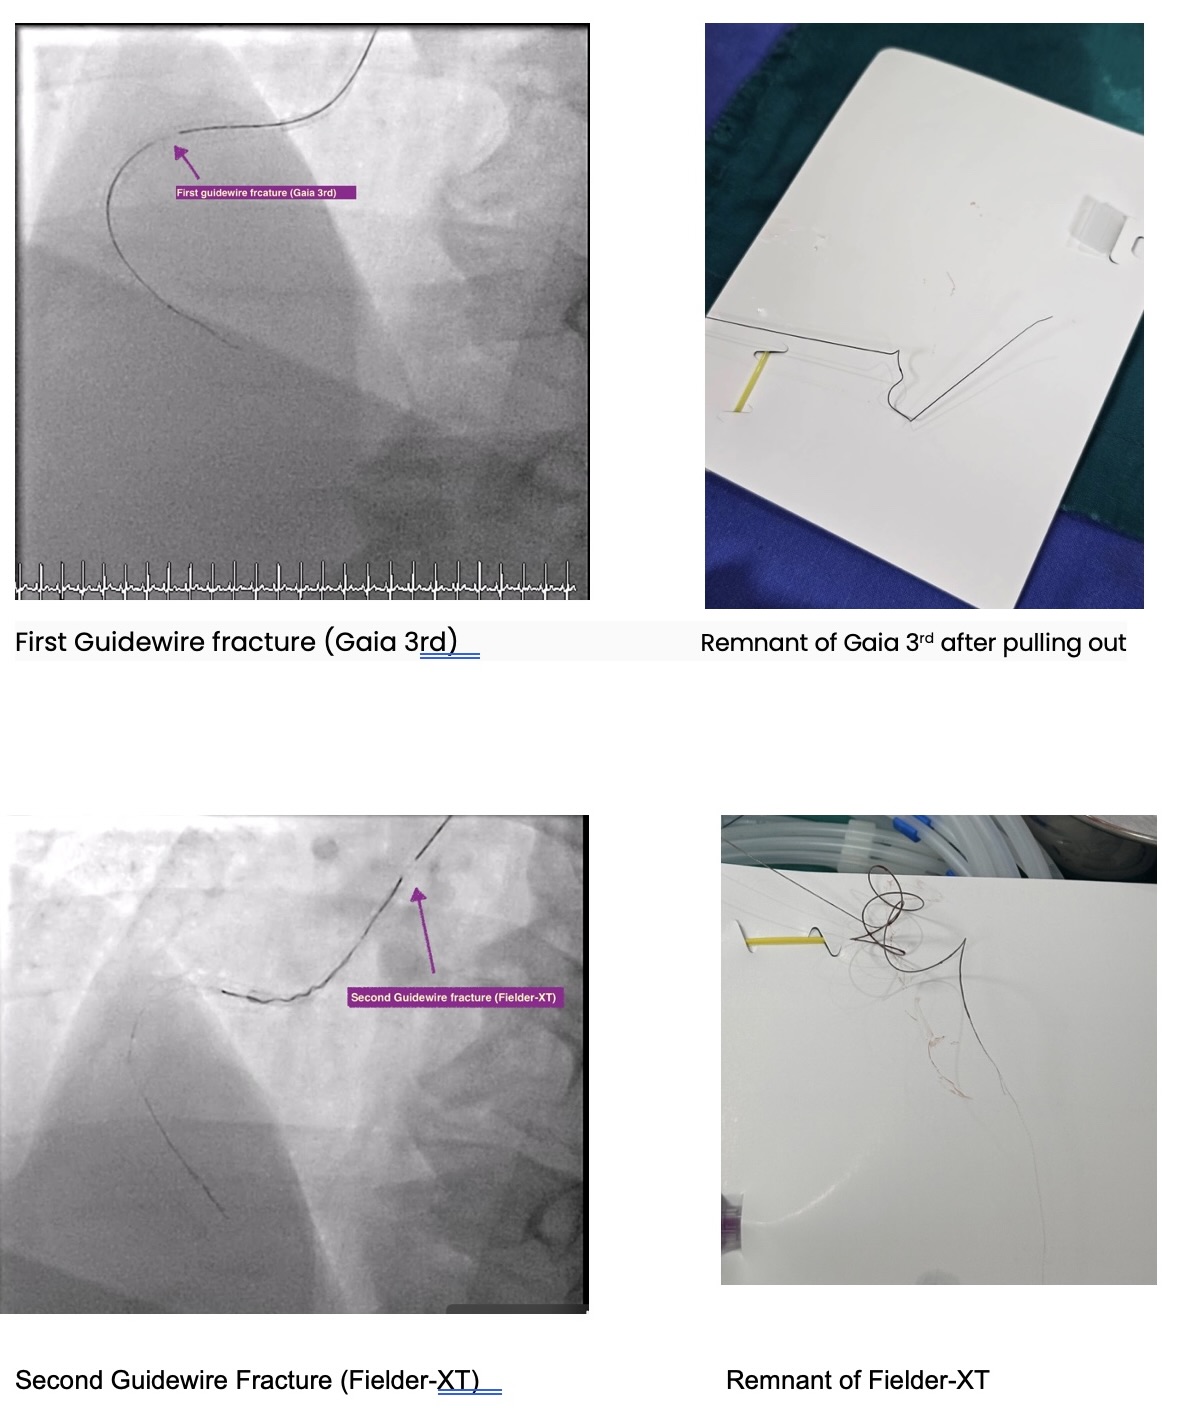

Microcatheter (Finecross) with Fielder XT to RCA, unable to pass the CTO lesion then changed to Gaia 2nd which was unsuccessful too and finally changed to Gaia 3rd. Gaia 3 rd guidewire got stuck at distal RCA. Snare catheter 8 mm was inserted to retrieve Gaia 3rd guidewire which was unsuccessful (Several attempts). Turntrac guidewire and Fielder-XT was inserted across the lesion to twist wire for Gaia 3rd retrieval, but failed and complete fracture of all three wires happened. Snare Size 8 mm was inserted for retrieval but failed.Smaller snare size 7 mm and 4 mm were inserted for retrieval but failed.Left femoral artery puncture with 8 Fr. Sheath. Guiding catheter JR 4.0/7 was used. Snare 8 mm and 15 mm via LFA could retrieve some part of wire. Decided to leave the wire at RCA due to several failed attempts. Angiogram was done before stopping the procedure. As we were removing the catheter, thin stretched guidewires were seen floating in the ascending aorta till descending aorta. Snare 15 mm could remove the wire floating in the aorta after several attempts.Final angiogram showed retained some parts of fractured guidewires and planned to leave it there. The patient was asymptomatic and hemodynamically stable.